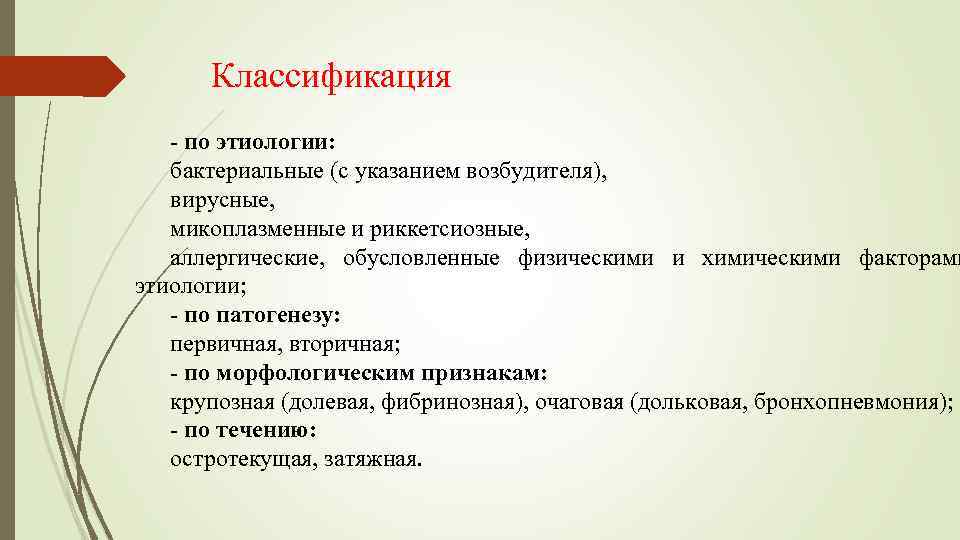

Классификация - по этиологии: бактериальные (с указанием возбудителя), вирусные, микоплазменные и риккетсиозные, аллергические, обусловленные физическими и химическими факторами этиологии; - по патогенезу: первичная, вторичная; - по морфологическим признакам: крупозная (долевая, фибринозная), очаговая (дольковая, бронхопневмония); - по течению: остротекущая, затяжная.

Классификация - по этиологии: бактериальные (с указанием возбудителя), вирусные, микоплазменные и риккетсиозные, аллергические, обусловленные физическими и химическими факторами этиологии; - по патогенезу: первичная, вторичная; - по морфологическим признакам: крупозная (долевая, фибринозная), очаговая (дольковая, бронхопневмония); - по течению: остротекущая, затяжная.